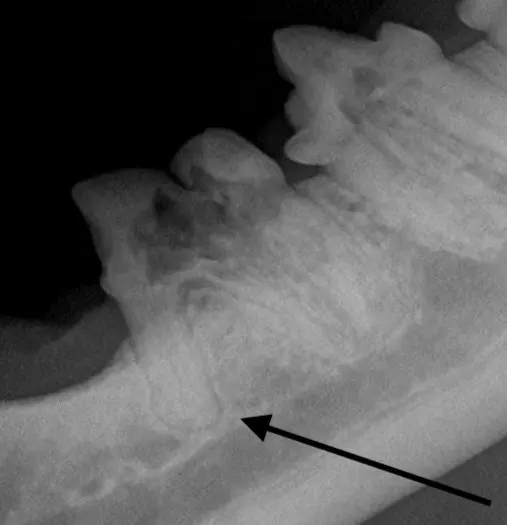

Iatrogenic fracture of the jaw can be a serious complication of surgical extractions and is most commonly associated with surgical extraction of mandibular canine teeth in dogs and cats and mandibular first molar teeth in dogs (Figure 10). These extractions can be difficult to perform, as the root apexes are often located in close proximity to the ventral cortex of the mandible, possibly leading to significant bone loss when severe disease is present and increasing the risk for iatrogenic fracture (Figure 11).

Pathologic fracture (arrow) secondary to severe periodontal disease of the right mandibular first molar tooth in a dog

Preoperative intraoral radiographs are critical for assessing fracture risk, especially prior to surgical tooth extraction, and can be used to modify the procedure or refer a patient with high fracture risk to a board-certified veterinary dentist.